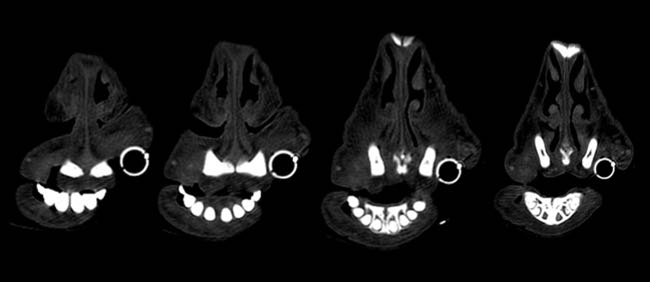

Given the clinical findings and prior experience with upper airway disease, ancillary tests were performed. Thermography did not identify consistent focal increases in temperature across the six animals, making common differentials such as chronic proliferative rhinitis (CPR) or enzootic nasal adenocarcinoma (ENA) less likely. Oestrosis had also been ruled out, as previous treatments targeting this condition failed to result in clinical improvement in the affected animals. Computed tomography (CT) of the head revealed increased soft tissue in the rostral nasal cavity, producing variable obstruction of the nasal meatuses in all sheep. On transverse CT images, soft-tissue thickening causing luminal narrowing was confined to the most rostral nasal cavity and decreased progressively on more caudal slices, where the nasal airway regained a wider lumen (Figure 3). This localisation of obstruction at the alar fold level explained the inspiratory dyspnoea and snoring.